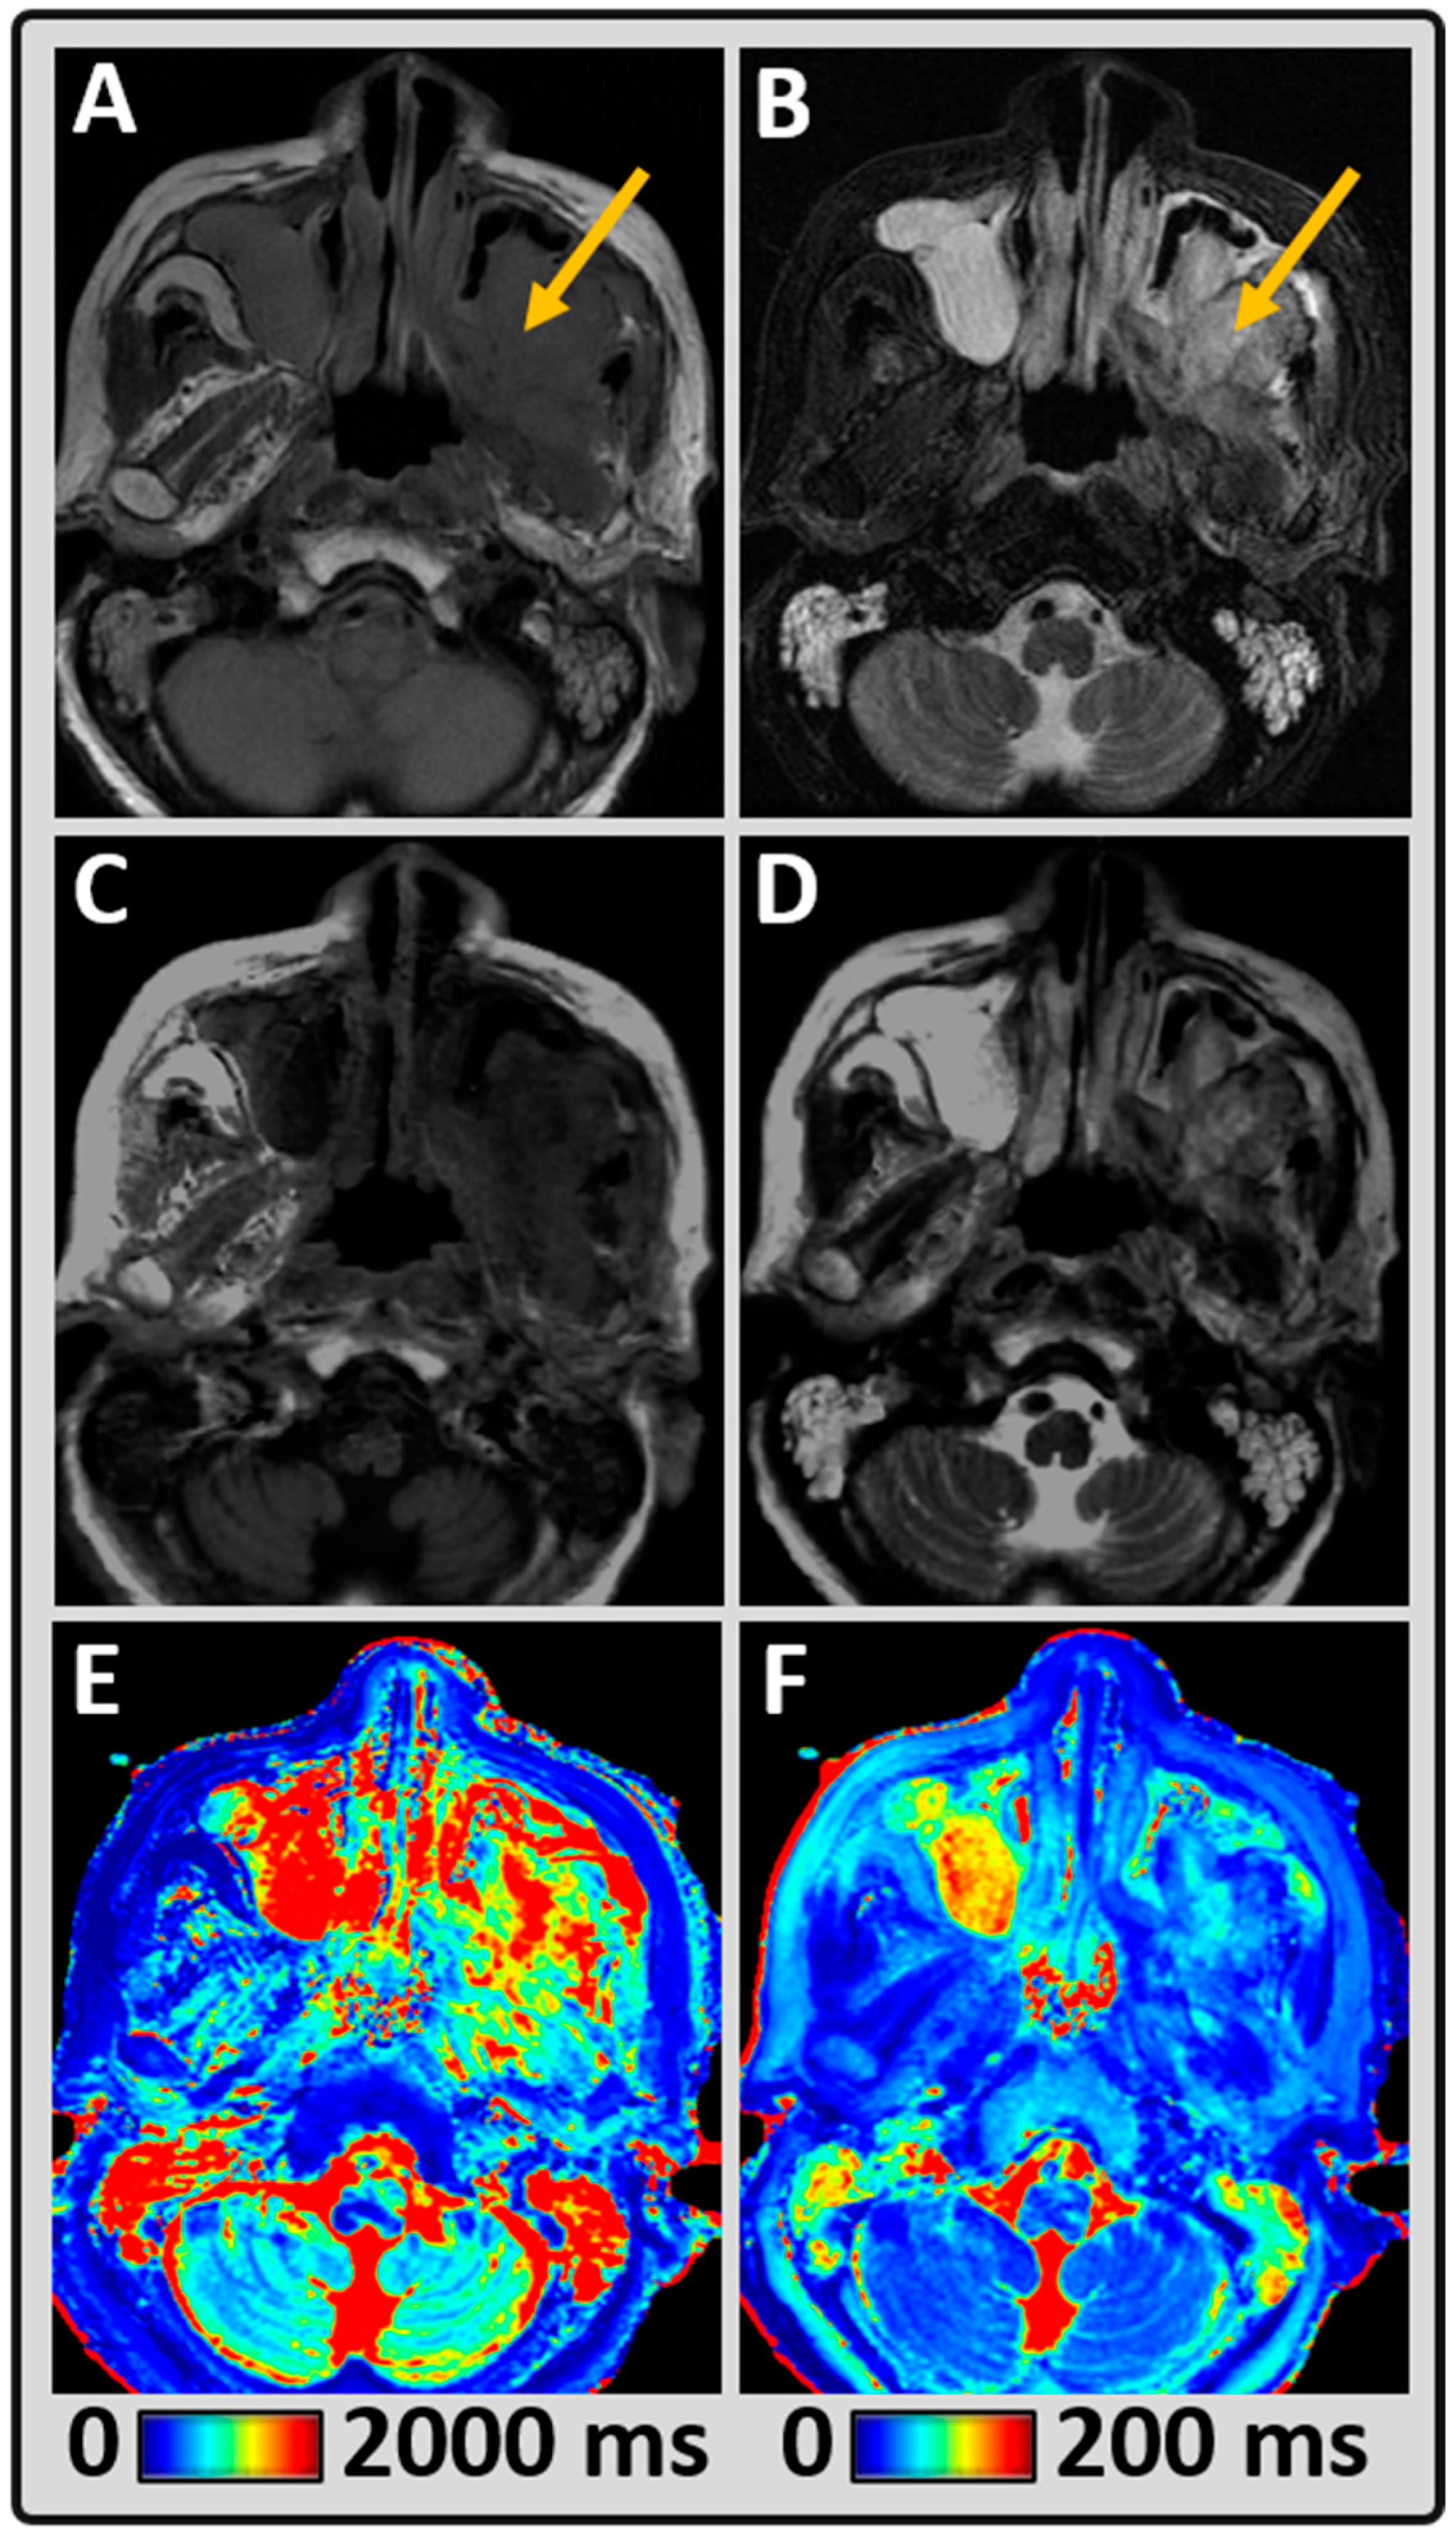

2.2. MRI Data Acquisition

2.3. Standard Head and Neck Imaging

2.4. Synthetic MR Imaging (MAGiC)

2.5. MRI Data Processing